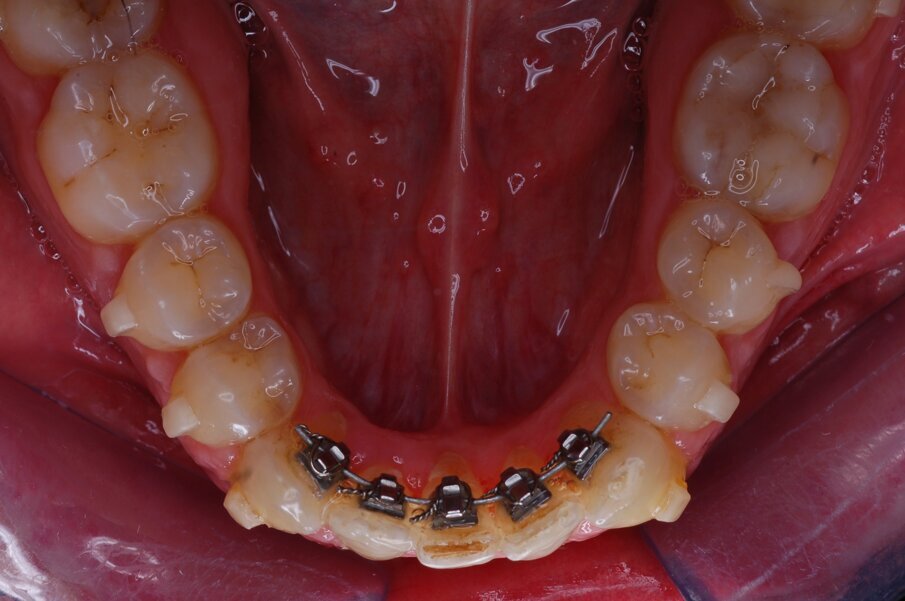

Diagnosi ed eziologia Un uomo sano di 39 anni si è presentato nel nostro studio ortodontico lamentando un aspetto dentale poco attraente e la paura della chirurgia ortognatica proposta da un altro ortodontista. Clinicamente, il profilo del paziente era rettilineo e la vista frontale non mostrava alcuna asimmetria facciale. L’esame funzionale non ha rivelato alcuna deviazione mandibolare o riduzione dei movimenti. Il paziente non aveva dolori articolari e non sono stati rilevati rumori articolari. Era presente una lieve occlusione molare bilaterale di Classe II, un morso aperto e un grave affollamento in entrambe le arcate. L’affollamento era particolarmente grave nell’arcata mandibolare, sebbene mancasse l’incisivo centrale mandibolare destro. Gli incisivi mascellari erano di piccole dimensioni, suggerendo una discrepanza dell’indice di Bolton se fossero stati presenti tutti e quattro gli incisivi mandibolari. Erano inoltre presenti un morso incrociato nella regione dell’incisivo laterale superiore sinistro e una grave rotazione distale del secondo premolare mandibolare sinistro (Figg. 1-8).

Figg. 1-8_Fotografie facciali e intraorali pre-trattamento.